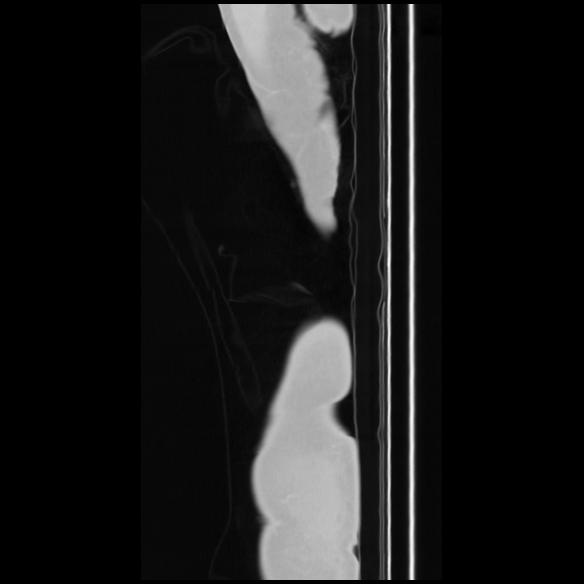

7 CUERPO,CE,Sagittal,3.000,CUERPO,Sagittal,